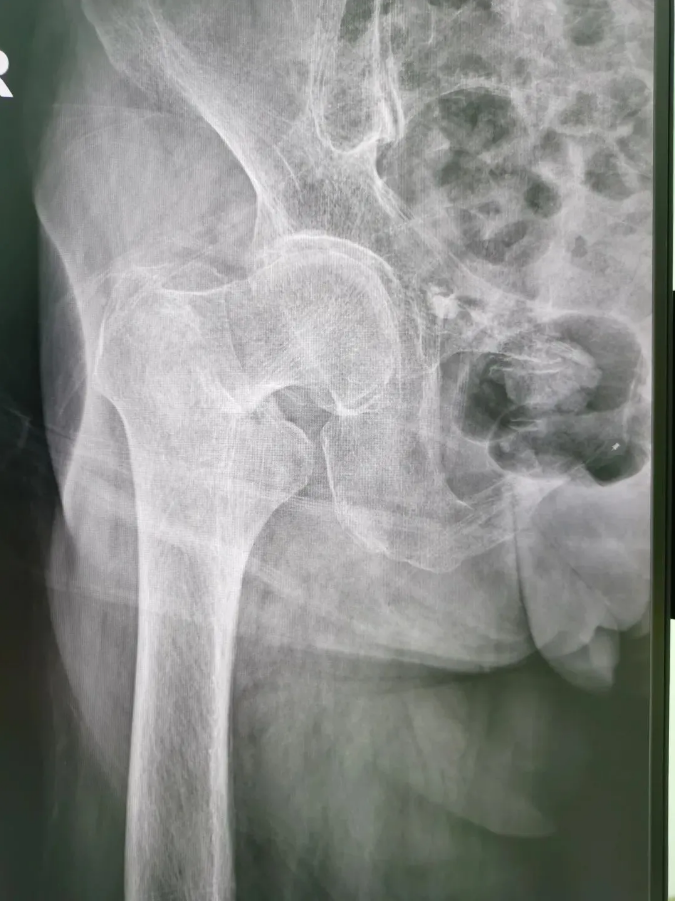

今年91歲的陳婆婆,9月份時在家不慎摔倒,右臀部著地,當下感到髖部劇烈疼痛并活動受限。為求進一步治療,到順德和平外科醫院骨三區就診,該區主任楊升平主任為其診療,被診斷為“右股骨頸骨折”,需進行右股骨頸骨折經皮閉合復位空心螺釘內固定手術。

術前X光

陳婆婆91歲的高齡,有高血壓和冠心病病史,通過傳統開刀手術治療風險較大。經骨三區專業醫療團隊討論,決定讓天璣?骨科機器人上場,輔助完成微創手術。